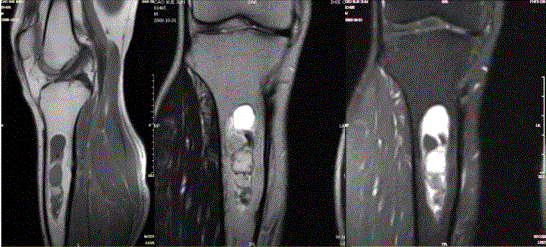

问题 患者女,20岁,右小腿疼痛1周。行双小腿正侧位CR,并行双小腿CT及MR扫描,见下图。 此病变最可能的诊断是

选项 A.骨囊肿 B.动脉瘤样骨囊肿 C.骨纤维异常增生症 D.骨巨细胞瘤 E.非骨化性纤维瘤

答案 C